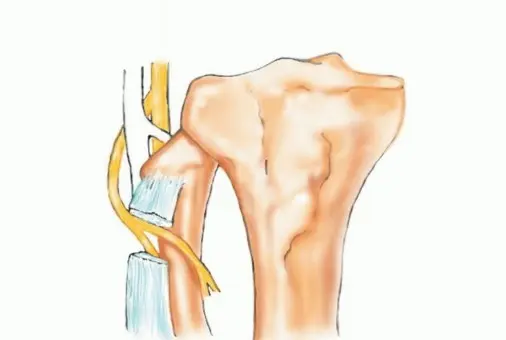

تُعد الشظية القريبة (الرأس والجزء العلوي من العظم) موقعًا رئيسيًا لالتصاق الرباط الجانبي الوحشي (LCL) ووتر العضلة ذات الرأسين الفخذية. هذه الروابط ضرورية لاستقرار مفصل الركبة الجانبي. الأهم من ذلك، أن العصب الشظوي المشترك يلتف حول قاعدة رأس الشظية ليدخل نفق العضلة الشظوية الطويلة، مما يجعله عرضة للإصابة أثناء جراحة الأورام في هذه المنطقة.

- الإجراء: يشمل إزالة الشظية القريبة، وغلاف عضلي رقيق من جميع الأبعاد، وموقع ارتباط الرباط الجانبي الوحشي (LCL). يتم الحفاظ على العصب الشظوي المشترك وفروعه الحركية، ويتم استئصال المفصل الظنبوبي الشظوي داخل المفصل.

- الحفاظ: يتم الحفاظ على العصب الشظوي والشريان الظنبوبي الأمامي عادةً.